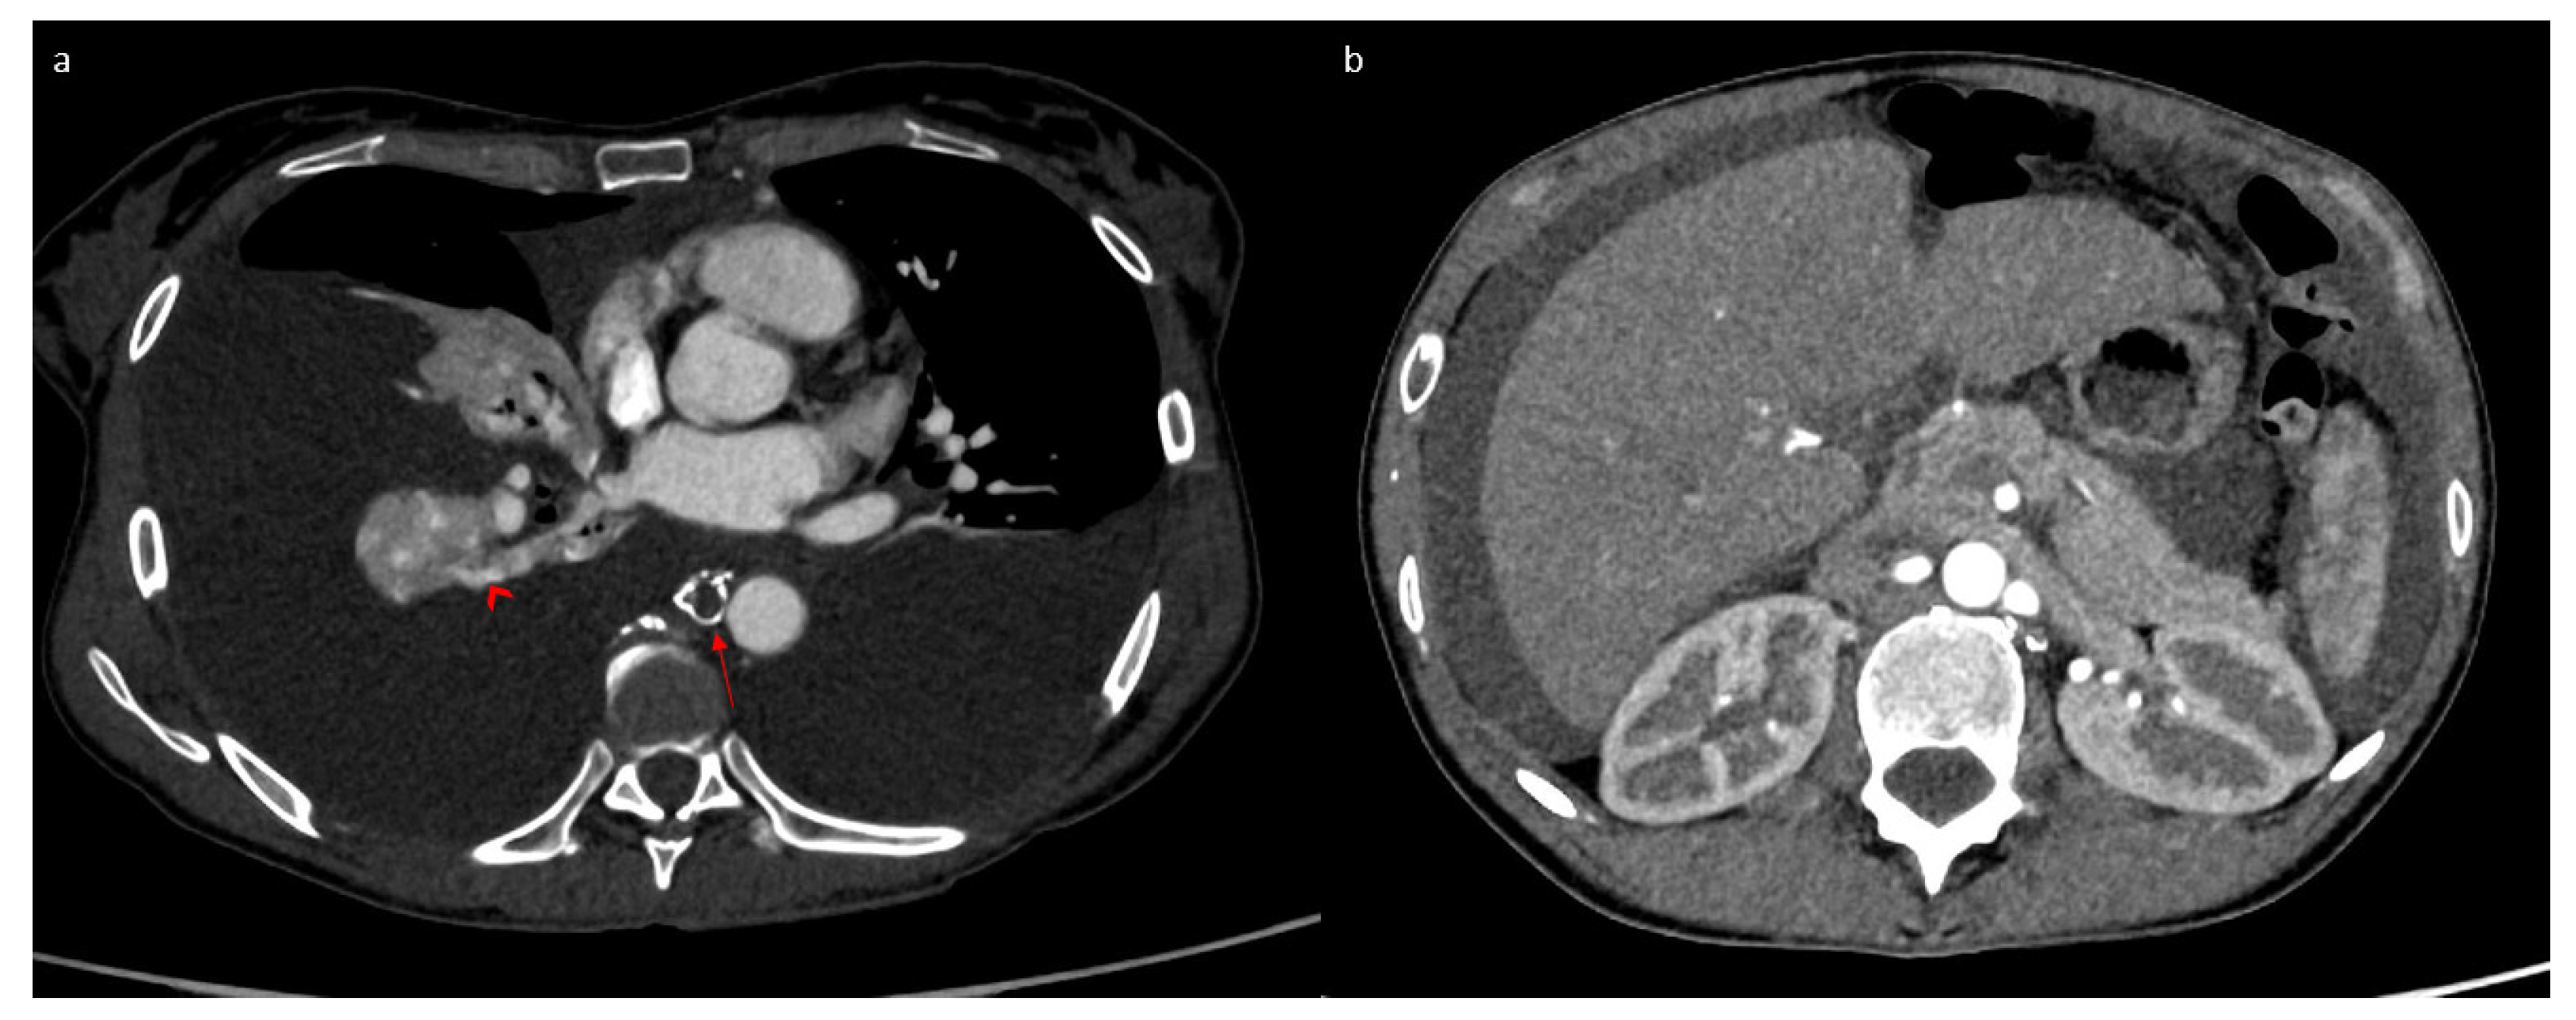

2. Case Report

3.1. Case Discussion and Physiopathological Hypothesis

3.2.3. Imaging